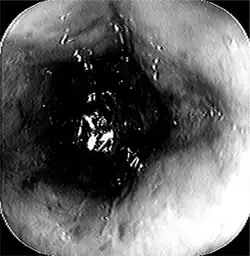

Acute esophageal necrosis-endoscopic view demonstrated progressive dusky and discolored esophageal mucosa.